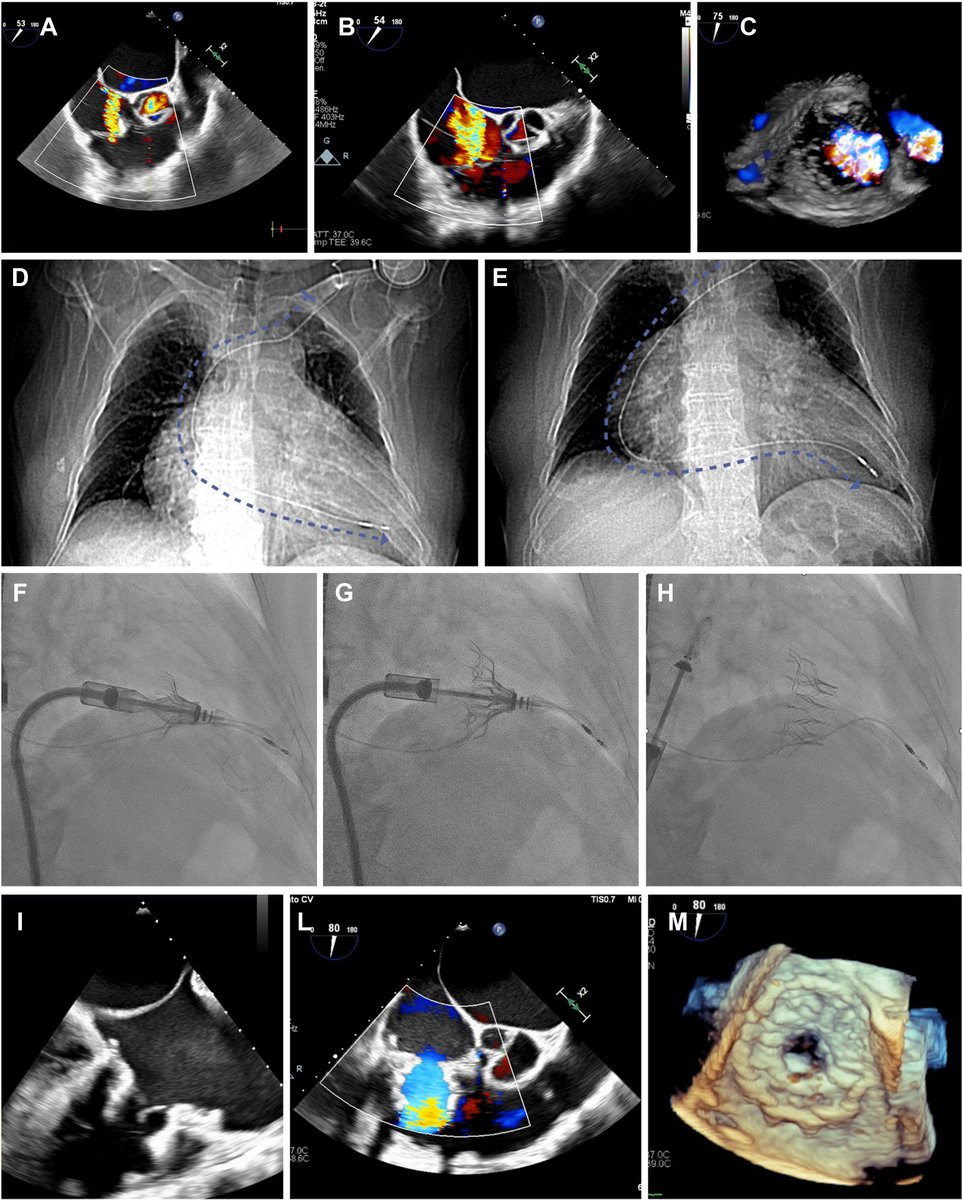

FANTASTIC MUST-READ #JACCIMG @JACCJournals SOTA review on Post #Evoque #TTVR Echo #TTE imaging. Comprehensive, practical! Download full paper here FREE for a LIMITED TIME! https://t.co/lfhJ0khJAw https://t.co/DgyCXnMOOF